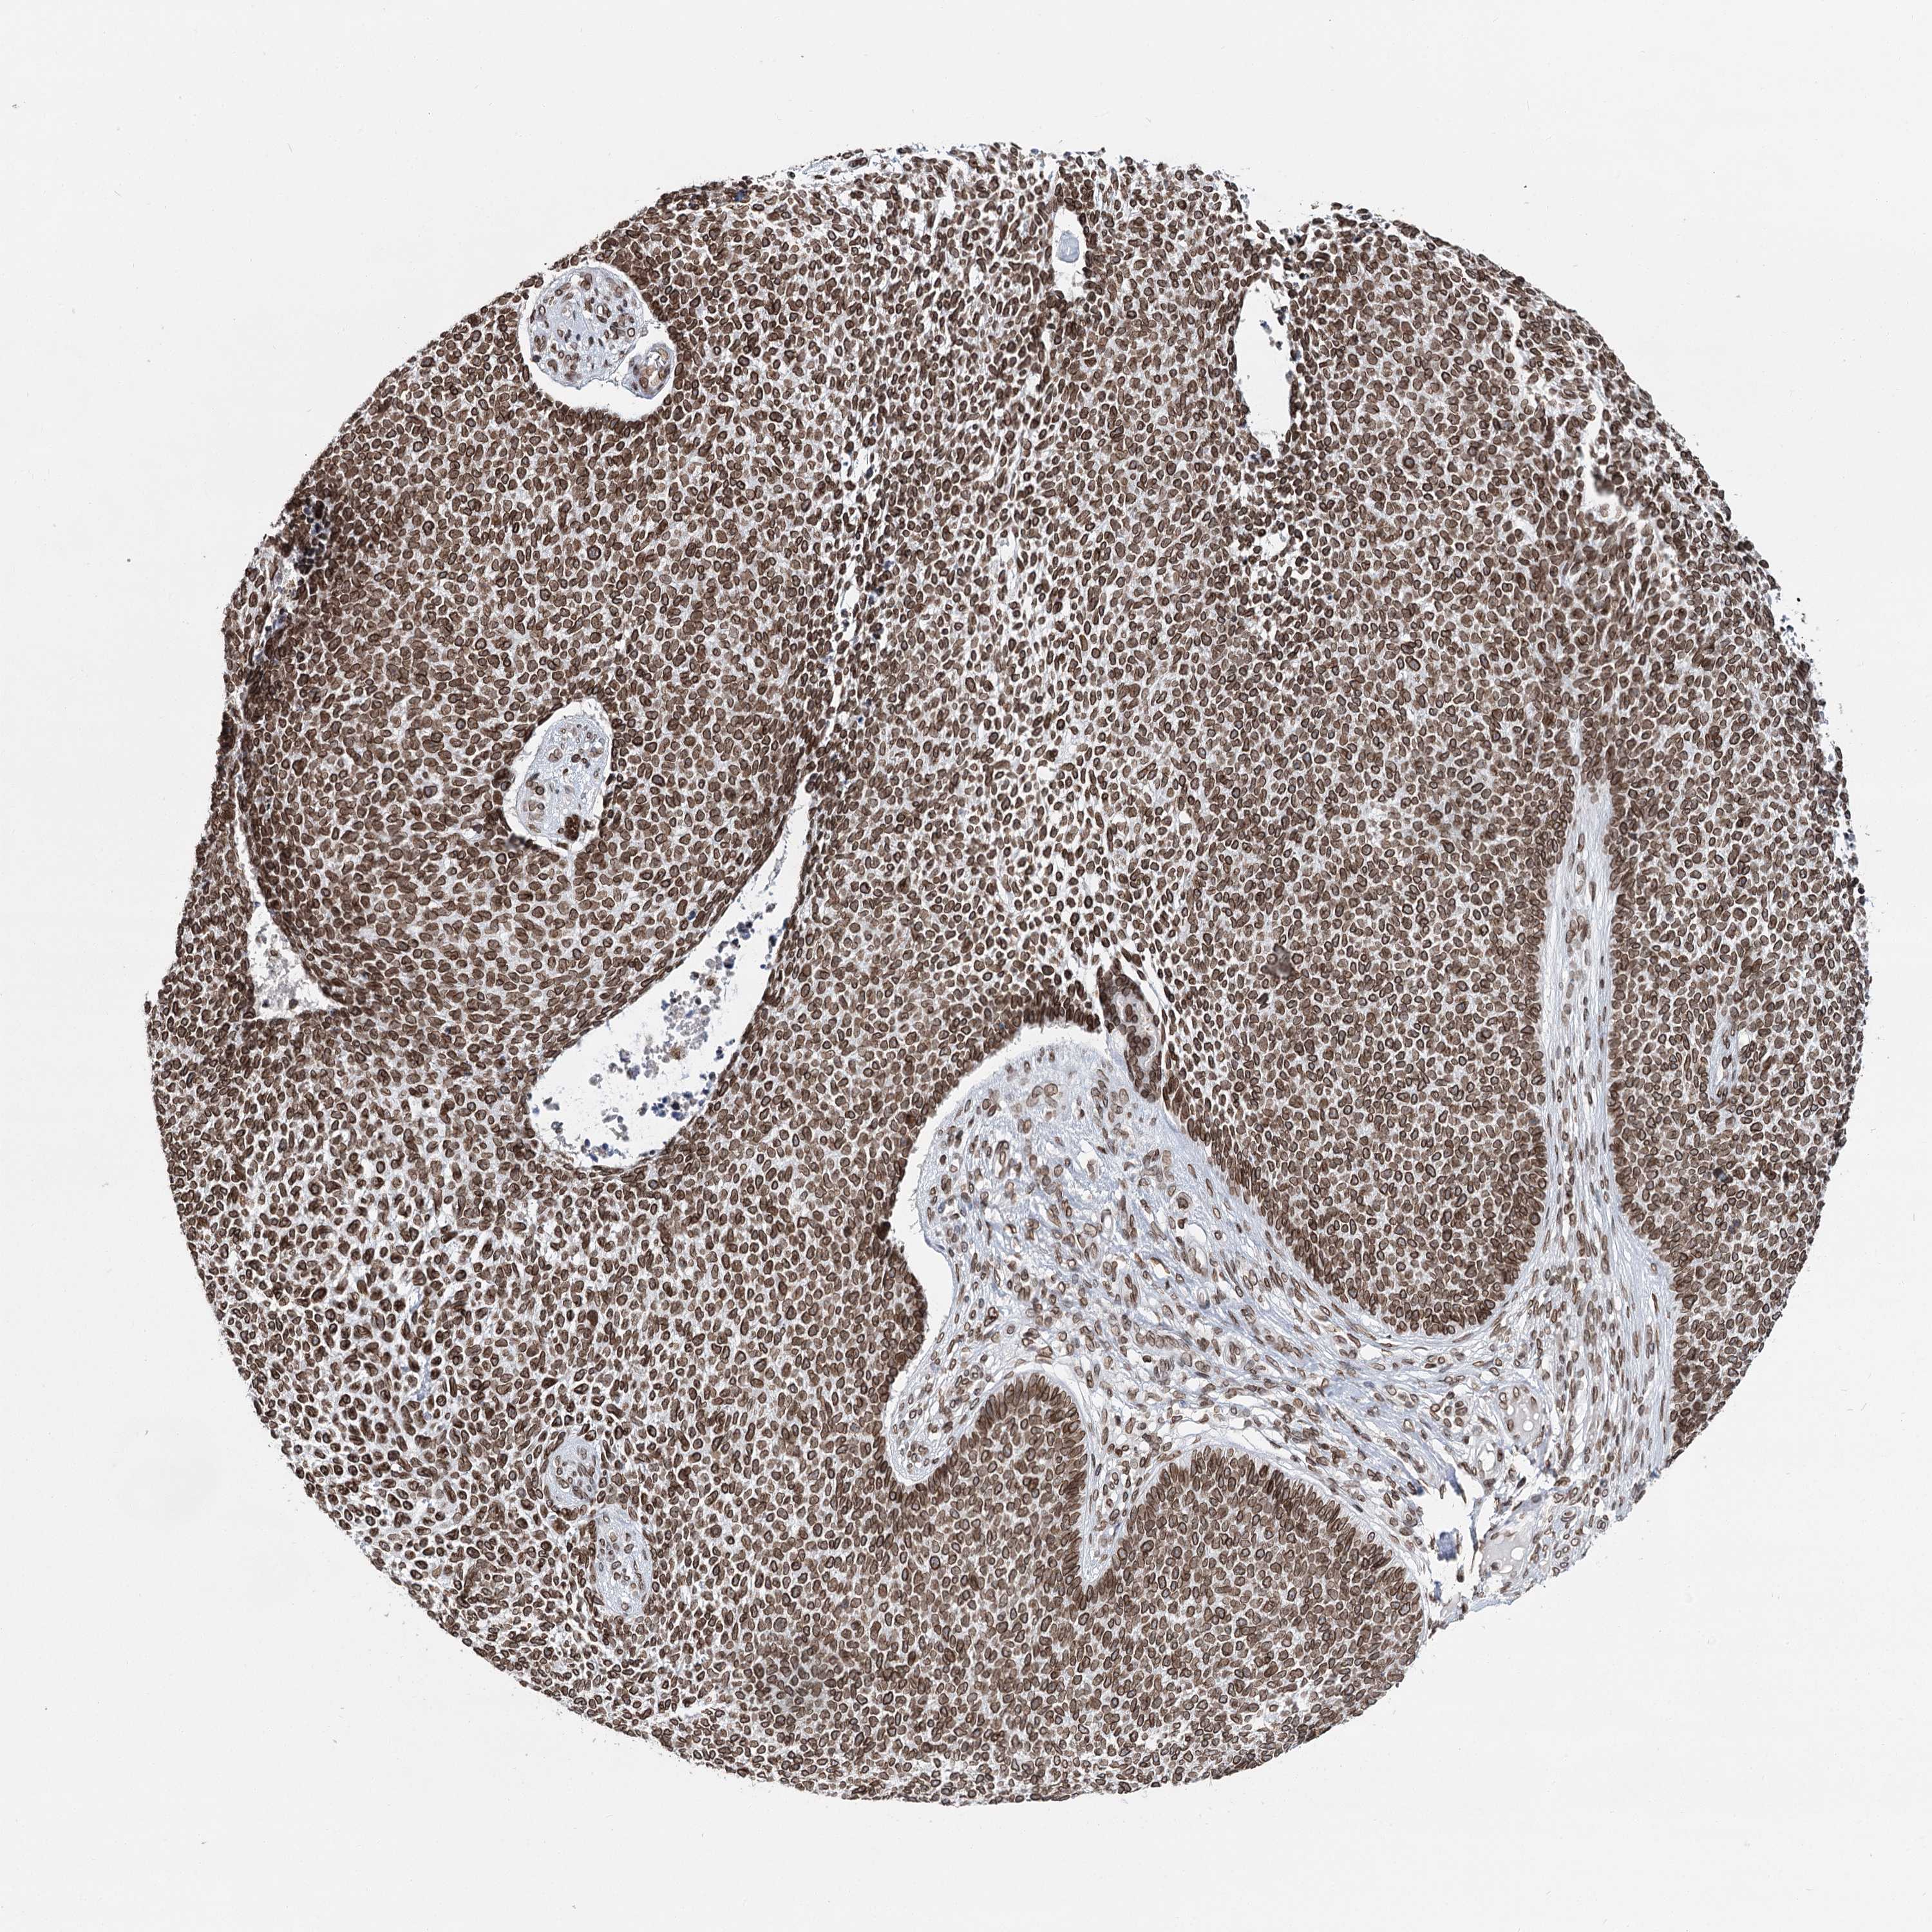

SKIN CANCER - Protein expressioni

A mouse-over function shows sample information and annotation data. Click on an image to view it in a full screen mode. Samples can be filtered based on level of antibody staining by selecting one or several of the following categories: high, medium, low and not detected. The assay and annotation is described here.

Antibody staining in the annotated cell types in the current human tissue is reported as not detected, low, medium, or high, based on conventional immunohistochemistry profiling in selected tissues. This score is based on the combination of the staining intensity and fraction of stained cells.

Each image is clickable and will lead to virtual microscopy that enables deeper exploration of all samples and also displays staining intensity scores, fraction scores and subcellular localization as well as patient and tissue information for each sample.

Antibody HPA038091

Staining

High

Intensity

Strong

Quantity

>75%

Location

Nuclear

Squamous cell carcinoma, metastatic, NOS

Squamous cell carcinoma, NOS